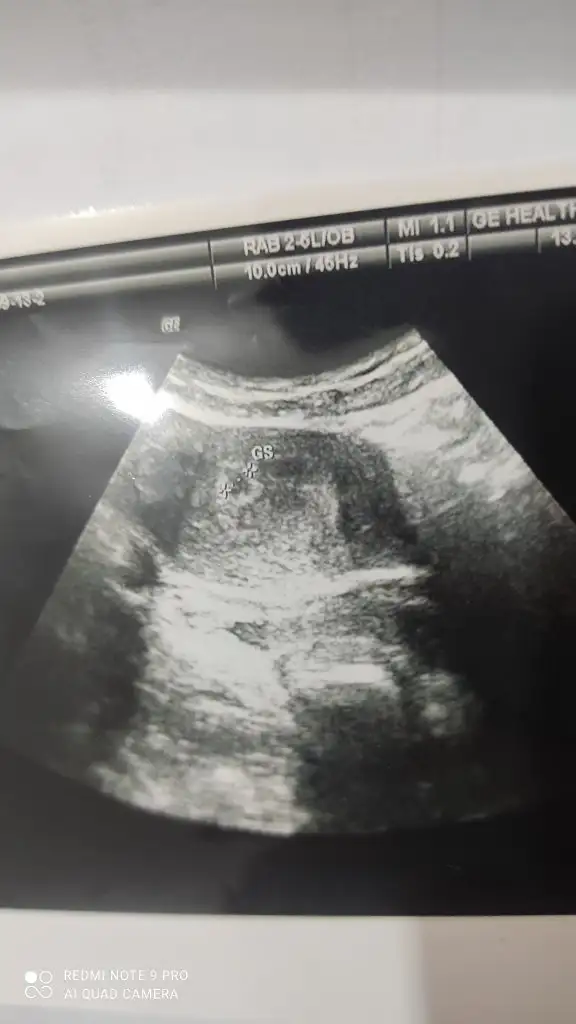

1) neyi yorumlayalım?Ultrason görüntüsu arkadaşlar. Dört hafta dört günlük Muş. Bilgisi olan yorumlayabilir mi?

Ederim dua canim. Rabbim sana da versin. Doktor iki tane kese var gibi ama emin değil tam dedi. Daha dört hafta dört günlük canımm. Bilemedim ikiz miDoktor iki tane mi kese var dedi? İkiz gebeligin kendini belli etmesi 5. 6. haftalarda gerçekleşirmiş.İnsAllah olurBenim icin de dua eder misin

Evet emin değilim dedi. Sonradan kayboladabiliyor Muş. Bende emin olamadımKesenin yanında bir kese daha var gibi ama kanama alanı da olabilir o. Bu yüzden doktor emin konuşmamış.

Şekline göre bence kanama alanı. Bende de bu şekilde çıkmıştı. Bir sonraki kontrolde belli olur zaten.Evet emin değilim dedi. Sonradan kayboladabiliyor Muş. Bende emin olamadım